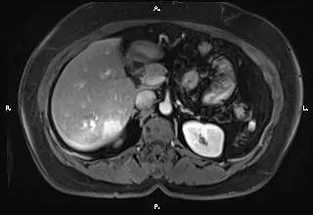

МРТ (магнитно-резонансная терапия) – основной метод диагностики глиоза головного мозга. Она необходима для того, чтобы определить месторасположение очага болезни. Благодаря этой процедуре врач даже может узнать, когда именно началось распространение заболевания.

Иногда только благодаря МРТ, врач может рассказать о причинах образования глиоза. Но более часто для этого нужны и другие исследования. Одним из них может быть компьютерная томография.